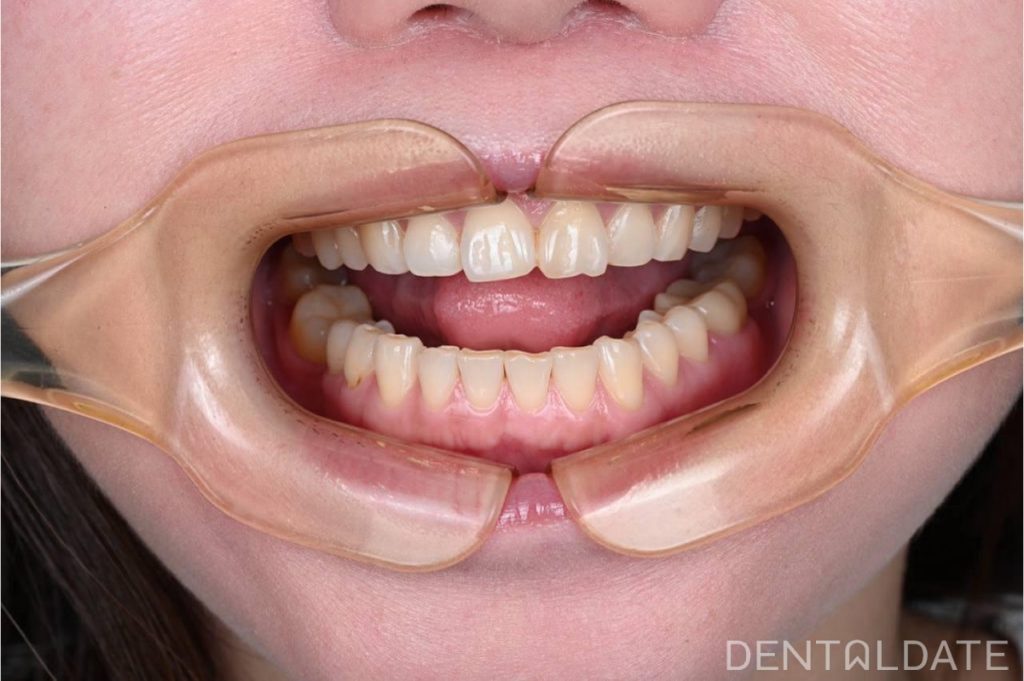

Complex treatment of TMJ arthrosis with orthodontic correction

In this clinical case, we want to demonstrate an approach focused on optimizing treatment timelines for temporomandibular joint (TMJ) osteoarthritis. The patient was diagnosed with TMJ osteoarthritis, confirmed by condylography and CT imaging.

During the splint therapy phase, we observed significant positive changes within just three weeks, including a reduction in symptoms and improved joint function. However, full treatment and joint stabilization require a much longer period.

To make the most of the adaptation phase, we simultaneously initiated orthodontic correction of the upper jaw. This approach allows us to significantly shorten the overall treatment time and achieve faster, more effective results.

This clinical case highlights the importance of a comprehensive approach and strategic treatment planning for TMJ disorders, enabling optimized timelines and improved therapy outcomes.